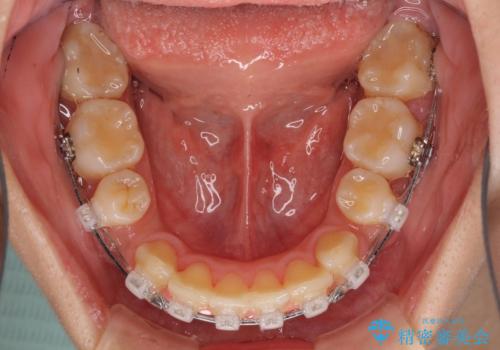

- クリアブラケット

- 上下前歯を部分矯正したところ出っ歯になってしまったとのことで来院された患者様です。

上下左右第一小臼歯4本を抜歯して、積極的に口元を引っ込めるよう、ワイヤー装置にて矯正治療を行うこととしました。